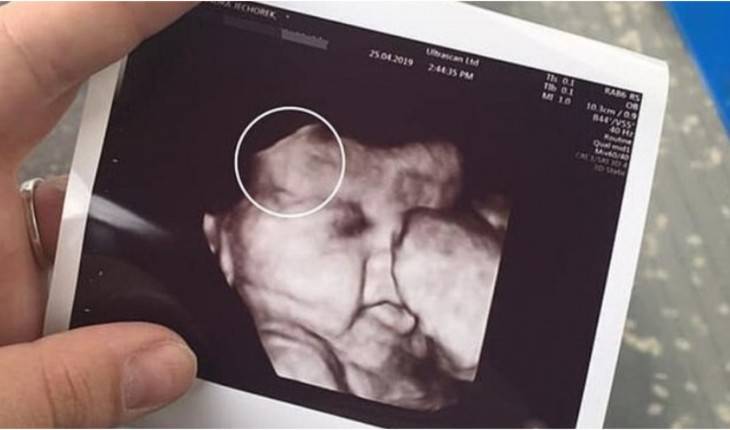

Lembra da bebê cabeluda no ultrassom? Ela nasceu e beleza encanta

Uma bebê surpreendeu a todos ao nascer com uma quantidade incomum de cabelo.